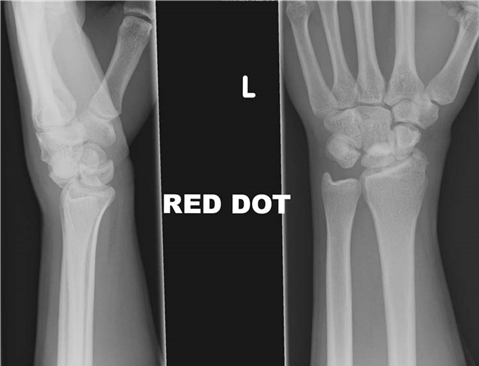

Pre-Operative Planning, Templating, and Patient Positioning

Thorough preoperative planning is critical to achieving optimal outcomes and minimizing complications. The clinical examination must document the exact degree of active and passive extension deficit at the MCP, PIP, and DIP joints using a goniometer. The skin must be meticulously assessed for dimpling, pitting, and the presence of nodules, as severe skin involvement may necessitate a dermofasciectomy rather than a standard regional fasciectomy. A detailed neurovascular examination is mandatory; two-point discrimination should be recorded for every digit, and an Allen’s test must be performed to ensure adequate collateral arterial flow, particularly if digital artery injury is a risk or if the digit has been chronically contracted.